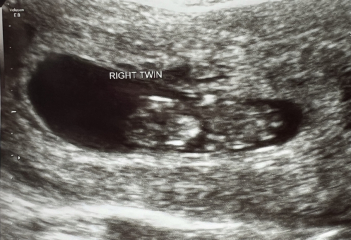

Hi everyone! Sorry I've been quiet on here, half term, a 6 year old and a twin pregnancy to contend with haha! We had another private scan today - I'll be 11 weeks tomorrow and there are two happy healthy wriggly babies in there! Xxx